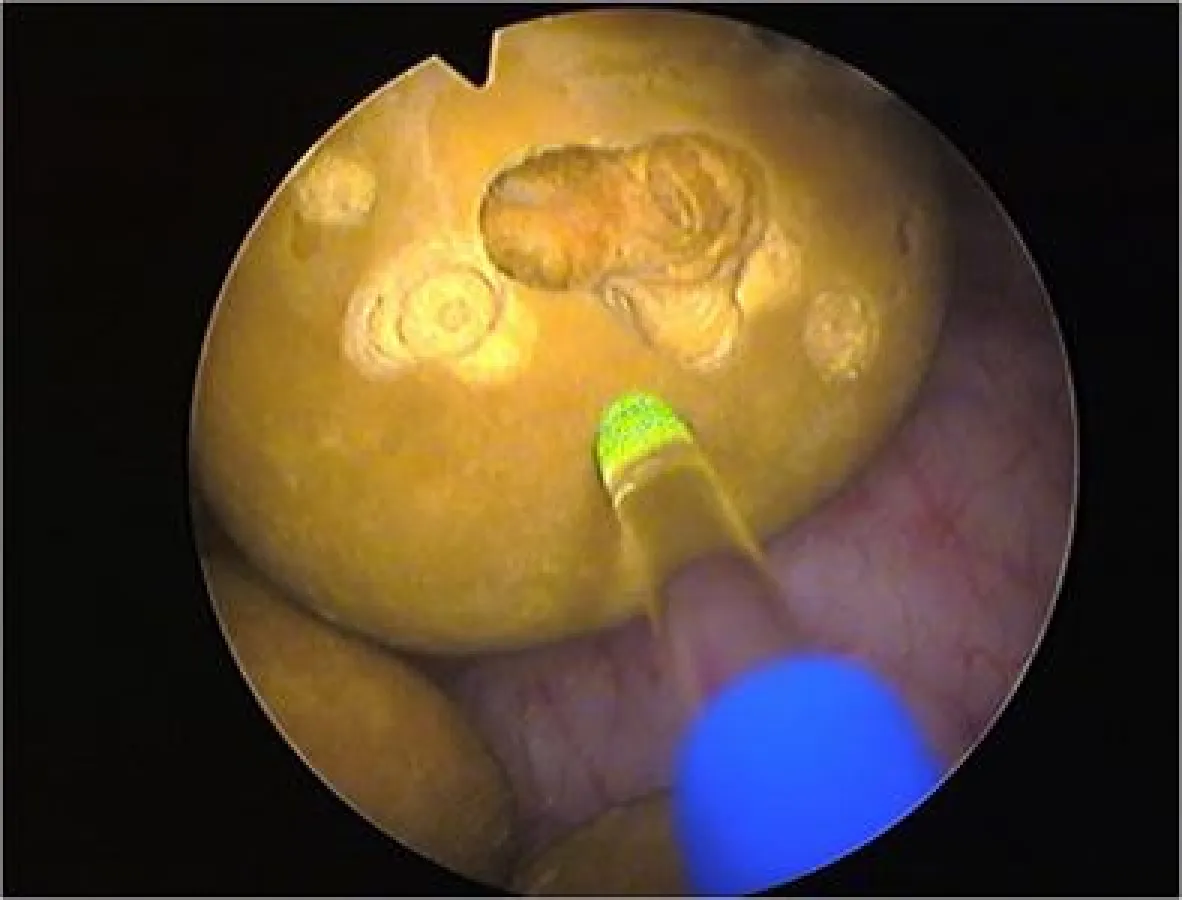

Die Klinik, seit vielen Jahren Vorreiter in Deutschland bei alternativen, schonenden Prostata-Behandlungsmethoden, geht nun einen ganz anderen Weg: Statt der klassischen OP nutzt sie einen neu entwickelten, so genannten Holmium-YAG-Laser des deutschen Herstellers Wolf zur Therapie. Die Faser eines ‚MegaPuls 30+’-Lasers wird mittels Zystoskop, einem Instrument zur Blasenspiegelung, über die Harnröhre in die Blase geleitet und zerstört dort mit gepulsten Energiestößen von 200 bis 4000 Millijoule (mJ) die Blasensteine. „Wir durchfahren während der Behandlung ein Impuls-Spektrum von 3 bis 25 Hertz, da jeder Stein anders aufgebaut ist und jeder Stein bei einer anderen Impulsfolge zerplatzt“, beschreibt der Urologe Dr. Martin Löhr das Verfahren. Jeder Puls ist dabei mit 150 bis 850 Mikrosekunden (µs, Millionstel Sekunde) extrem kurz. Je nach Zahl und Größe der Blasensteine dauert eine Laser-Behandlung zwischen wenigen Minuten und einer Stunde. Da sich der Patient in einer leichten Narkose befindet, spürt er von alledem nichts.

Nach dieser so genannten Laser-Lithotripsie werden die Stein-Überreste abgesaugt oder fließen mit dem Harn ab. „Die für den Harnstau verantwortliche Prostata-Vergrößerung behandeln wir wenige Woche später sehr schonend mit unserem Greenlight-Laser, der mit seiner Leistung von 180 Watt auch Prostata-Drüsen von deutlich über 100 Gramm schafft“, so Dr. Löhr. Das grüne Laserlicht trägt dabei das überflüssige Gewebe nach dem Prinzip der Photoselektiven Vaporisation schonend ab, so dass der Patient schon am Folgetag wiederhergestellt ist und seiner Arbeit nachgehen kann – ohne langwierige und belastende Operation mit gravierenden Nebenwirkungen. „Auch das Risiko einer Einschränkung der Potenz oder Zeugungsfähigkeit ist bei den beschriebenen Laser-Verfahren extrem gering“, bestätigt der Kollege Dr. Thomas Dill.